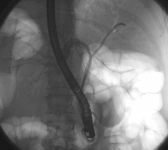

Malign tümörler, kanserli hücrelerin kontrolsüz bir şekilde bölünmesi ve çoğalması sonucu oluşan, çevre dokulara zarar verebilen ve metastaz yapma potansiyeline sahip olan tümörlerdir. Bu tümörler, vücutta çeşitli sistemleri etkileyebilir ve ciddi sağlık sorunlarına yol açabilir. Bu makalede, malign tümörlerin belirtileri, tanı yöntemleri ve tedavi seçenekleri ele alınacaktır. Malign Tümörlerin BelirtileriMalign tümörlerin belirtileri, tümörün türüne, büyüklüğüne ve bulunduğu bölgeye göre değişiklik gösterebilir. Ancak, genel olarak aşağıdaki belirtiler sıkça gözlemlenmektedir:

Bu tanı yöntemleri, malign tümörlerin varlığını belirlemek ve tümörün türünü, evresini değerlendirmek amacıyla kullanılmaktadır. Erken tanı, tedavi sürecinde büyük bir öneme sahiptir. Malign Tümörlerin Tedavi SeçenekleriMalign tümörlerin tedavisi, tümörün türüne, evresine ve hastanın genel sağlık durumuna bağlı olarak değişiklik göstermektedir. Başlıca tedavi yöntemleri şunlardır: